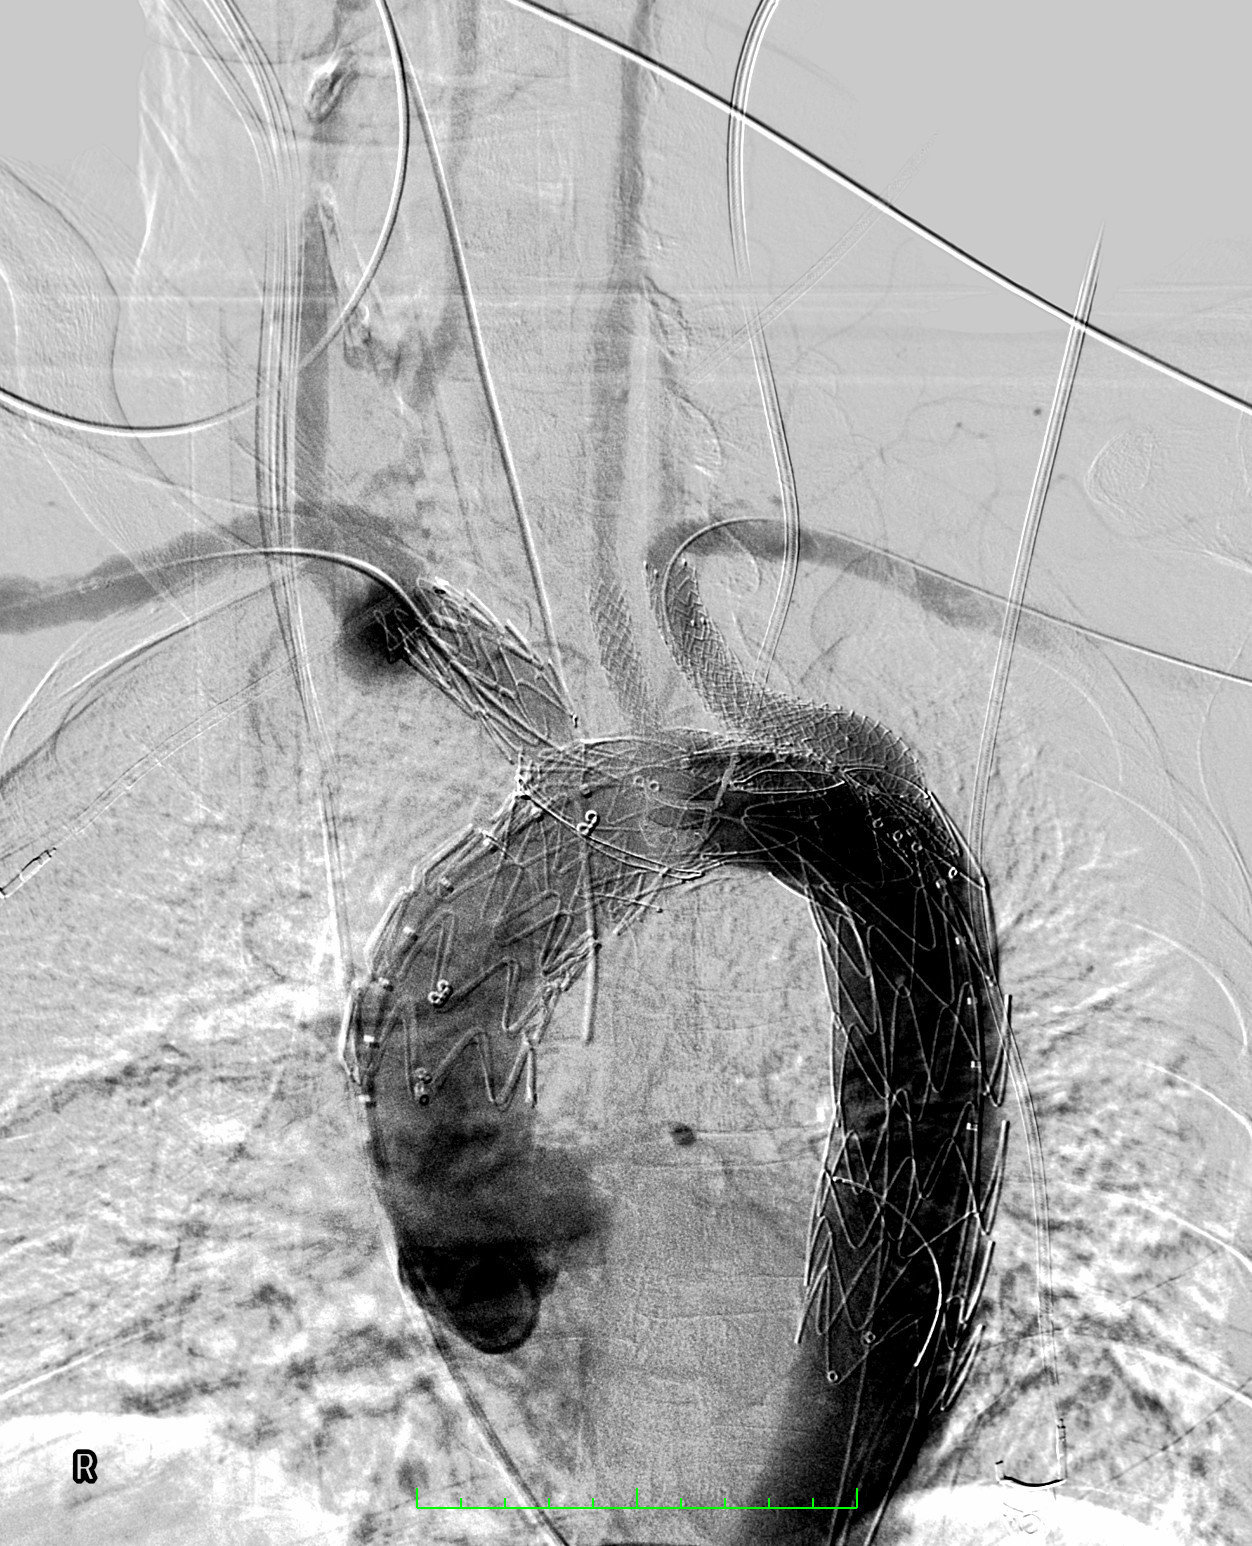

Pod koniec marca br. wykonano pierwszą w województwie pomorskim i trzecią w Polsce operację patologii łuku aorty systemem NEXUS TRE. Dzięki takiej procedurze udało się choremu uniknąć rozległej operacji kardiochirurgicznej z otwarciem klatki piersiowej oraz krążeniem pozaustrojowym.

Zespół chirurgów naczyniowych „Szpitali Pomorskich” rozpoczął w 2023 r. zabiegi endowaskularne w obrębie łuku aorty, dołączając tym samym do elitarnych oddziałów w Polsce. Obecnie ma na koncie liczne, wykonane z powodzeniem zabiegi.

Zabieg był dodatkowo wyjątkowy, gdyż chory obarczony jest niedrożnością obu tętnice szyjnych, odpowiedzialnych za dostarczanie krwi do mózgu. Czas zabiegu oraz zaangażowanie anestezjologa dr Pawła Dutki miał tu decydujące znaczenie — mówi doktor Ryszard Zając, ordynator Oddziału Chirurgii Naczyniowej Szpitala św. Wincentego a Paulo w Gdyni

Udaną operację przeprowadzono ze wsparciem specjalisty klinicznego, doktora Alana Abilio, który przyjechał z Brazylii. Chory bez powikłań udał się w piątej dobie do domu.